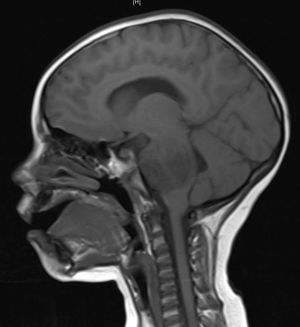

التشخيص

عن عمل أشعة مقطعية للرأس للتأكد من وجود ورم بعد عمل الفحص السريري. كما ان فحص الجهاز العصبي مهم حتى يمكن معرفة مكان الإصابة في الدماغ.

ومن الفحوص الأخرى التي يمكن اجراؤها هو حقن مادة ملونة في احد الشرايين المغذية للمخ ثم تصوير الرأس حيث تظهر كافة الشرايين هناك، وهذا الفحص يجرى عادةً إذا كان هناك نية لإجراء عملية جراحية لاستئصال الورم.